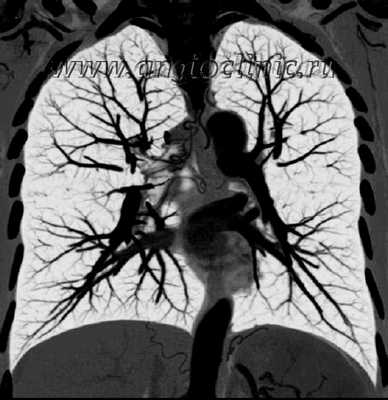

Ангиография легких

Ангиограмма-это рентгеновское изображение кровеносных сосудов. Она также называется артериограмма. Она делается, чтобы посмотреть на кровеносные сосуды, которые имеют проблемы. Легочная ангиограмма-это ангиограмма кровеносных сосудов малого круга легких.

Процедура проводится с помощью специального контрастного вещества, вводимого в кровеносные сосуды. Доступ делается в паху или руке. Контраст проявляется на рентгеновской установки. Используется специальный цифровой рентгеновский ангиограф. Исследование снимается в режиме реального видео. Оно позволяет вашему врачу четко видеть сосуды легких и проблемы в них.

Ангиопульмонография - рентгеновское исследование легочных артерий, применяемое для выявления причин легочной гипертензии. Всем пациентам до операции на легочных артериях для оценки состояния легочного русла должна выполняться ангиопульмонография в двух проекциях.

Как проводится ангиография легких

Ангиогпульмонография начинается с выполнения пункции правой подключичной или яремной вены, в которую устанавливается интродьюсер 6 FR. По интродьюсеру на проводнике при помощи диагностических катетеров катетеризируются правые отделы сердца. Диагностический катетер устанавливается в легочный ствол в область бифуркации правой и левой главных легочных артерий. При помощи автоматического инжектора в легочную артерию вводится контраст. Далее для визуализации правой ЛА катетер устанавливается в правую главную ЛА и вводилось 40 мл контраста. Для визуализации левой ЛА катетер устанавливается в левую главную ЛА и вводится тот же объем контраста. Во время введения контраста пациент задерживает дыхание, хирург выполняет исследование легочной артерии в двух проекциях.

АНГИОПУЛЬМОНОГРАФИЯ

АНГИОПУЛЬМОНОГРАФИЯ (греческий angeion — сосуд, латинский pulmo — легкое и греческий grapho — пишу, изображаю; синоним: ангиопневмография, ангиография легких) — рентгенологическое исследование ветвей легочной артерии после их контрастирования.

Применяют две методики ангиопульмонографии: общую и селективную; разновидностью селективной ангиопульмонографии является концевая ангиопульмонография.

Рис. 1. Общая ангиопульмонография. Контрастное вещество введено катетером. Видны контрастированные сосуды легких. Справа в области ключицы и вдоль позвоночника виден введенный в сердце катетер

Рис. 2. Селективная ангиопульмонография. Катетер (виден под ключицей, вдоль позвоночника и в области сердца) введен в верхнезональную артерию правого легкого. Видны контрастированные сосуды верхней зоны

Для осуществления общей ангиопульмонографии контрастное вещество в количестве 50—70 мл вводят внутривенно (обычно через локтевую вену) или в полость правого сердца (см. Ангиокардиография) при помощи введенного через вену катетера (рис. 1). При селективной ангиопульмонографии (рис. 2) контрастное вещество вводят в одну из ветвей легочного ствола; для этой цели катетер проводят через правое сердце в легочный ствол и далее в легочную артерию. Для контрастирования одного легкого применяют 20—30 мл контрастного вещества, для исследования одной зоны — 10—15 мл.

Рис. 3. Концевая ангиопульмонография. Катетер (виден под ключицей, вдоль позвоночника и в области сердца) введен в верхнесегментарную артерию верхней зоны правого легкого. Видны концевые артериальные разветвления. Контрастированы пути венозного оттока данного сегмента

Селективная ангиопульмонография позволяет одновременно измерять давление в полостях сердца и легочного ствола и определять степень насыщения крови кислородом. При концевой пнгиопульмонографии катетер вводят в одну из сегментарных ветвей легочной артерии (рис. 3),после чего инъецируют 5—8 мл контрастного вещества. Кроме описанных методик, ангиопульмонография может быть выполнена путем чрескожной пункции бедренной или подключичной вены по способу Сельдингера (с последующим введением зонда).

Различают три фазы контрастирования сосудов легких: артериальную, продолжающуюся 3—5 секунд, капиллярную, или паренхиматозную, продолжительностью в 1-3 секунды, и венозную, длящуюся 4—7 секунд. Для изучения легочного кровообращения проводят серию снимков на сериографе по следующей примерной программе: 2 снимка в 1 секунду в течение 3 секунд, затем 1 снимок в 1 секунду в течение 10 секунд.

Ангиопульмонография - метод рентгенологической диагностики состояния лёгочного кровообращения путём введения рентгеноконтрастных веществ в артерии лёгких. Выделяют общую и селективную ангиопульмонографию. При общей ангиопульмонографии контрастное вещество вводят в ствол лёгочной артерии, при этом заполняются все сосуды малого круга кровообращения. При селективной контраст вводится лишь в одну из ветвей лёгочной артерии и оценивается состояние кровотока только одного лёгкого или его доли.